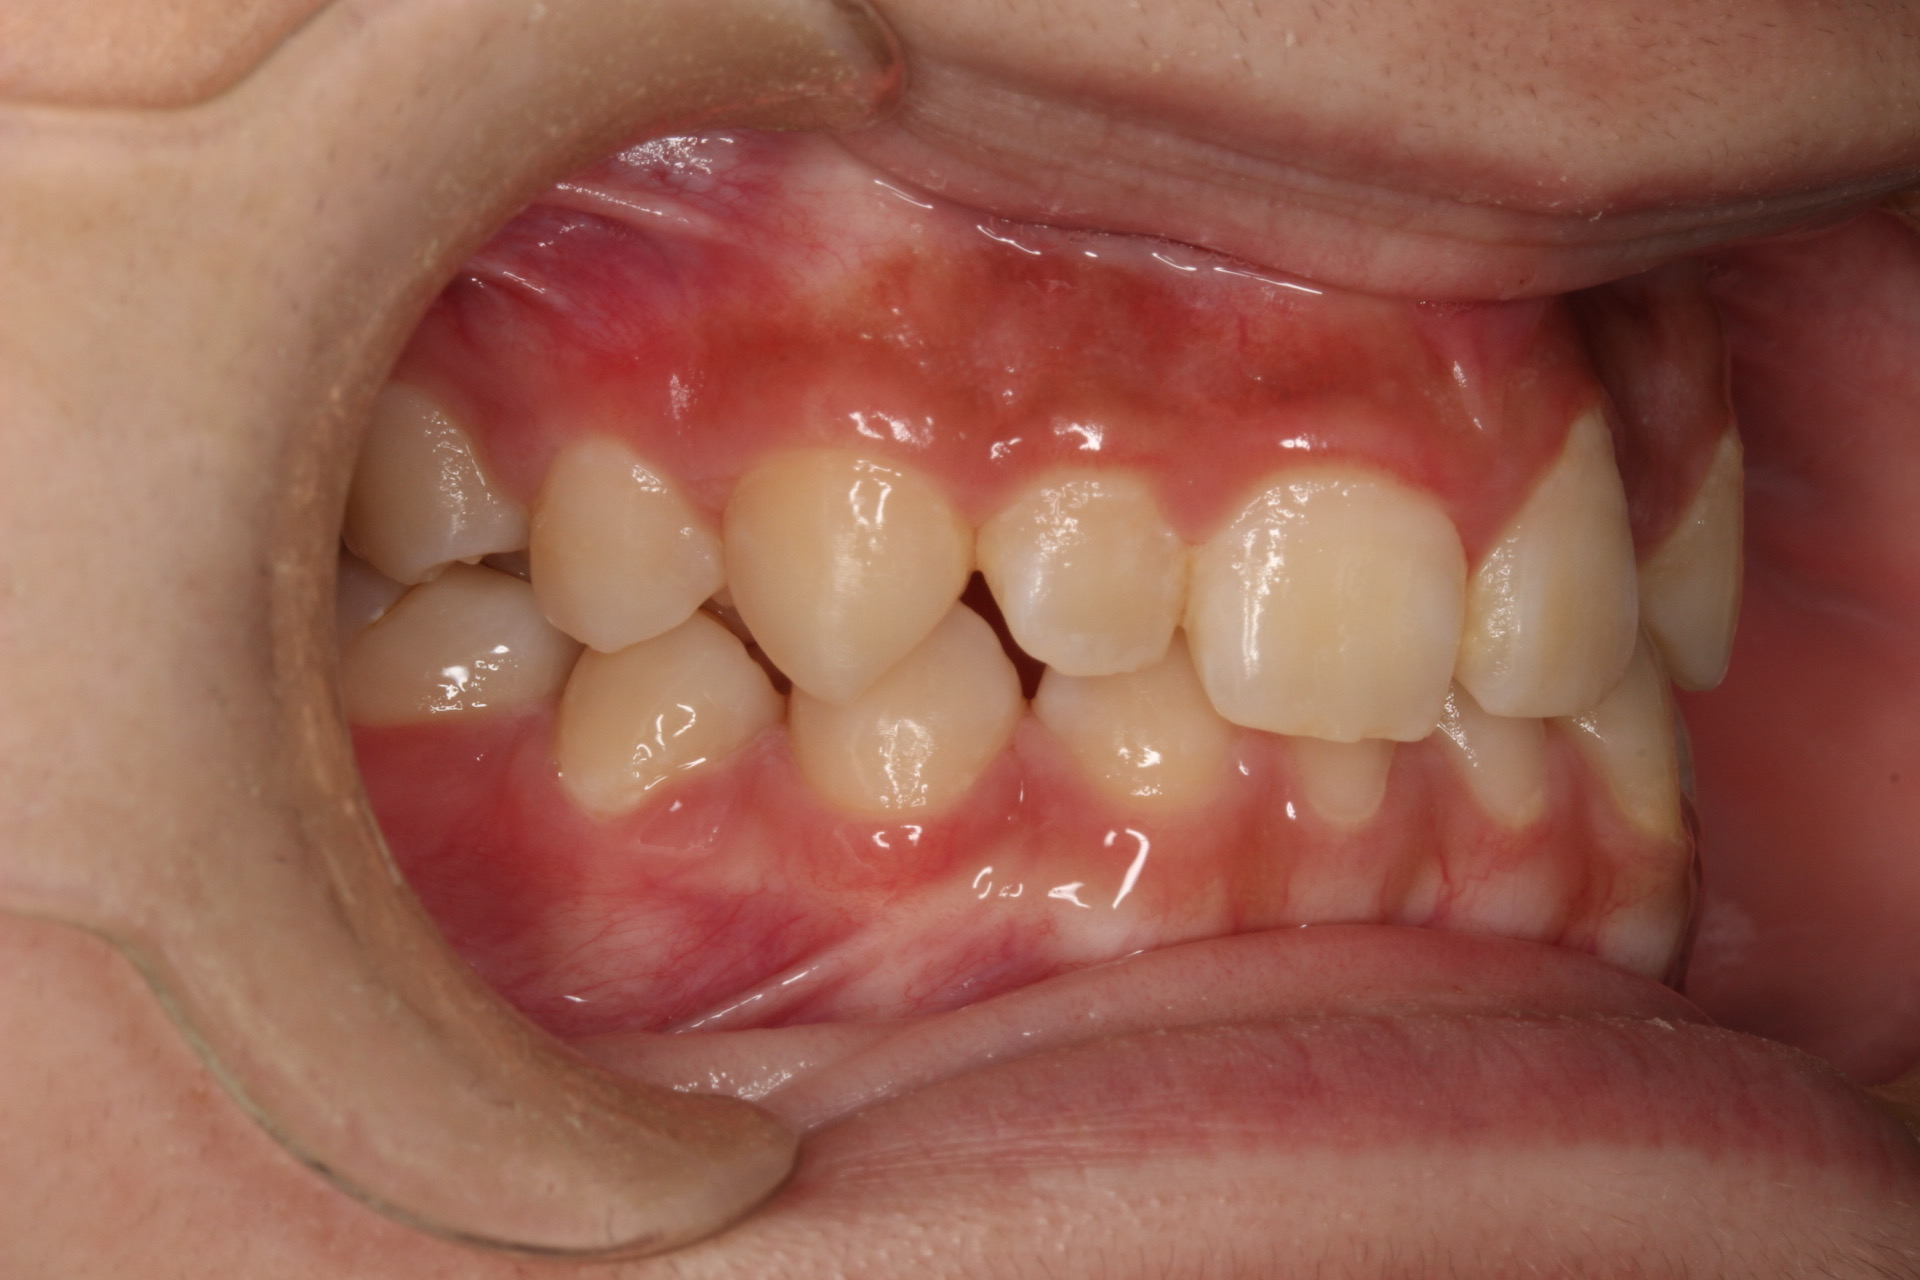

矯正術前:右側

| 主訴 | 上の歯が1本だけ奥に引っ込んでいることが気になる |

| 治療内容 | 患者様は、上の歯が1本だけ奥に引っ込んでいることを気にされており、矯正検査後Ⅱ級傾向の叢生と診断いたしました。ワイヤー矯正後に、インビザラインによる仕上げ矯正を行っております。 |